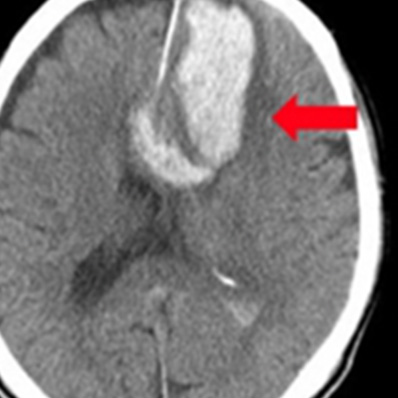

上から 急性硬膜下血腫、

脳挫傷、外傷性くも膜下出血

皮質下出血

被殻出血